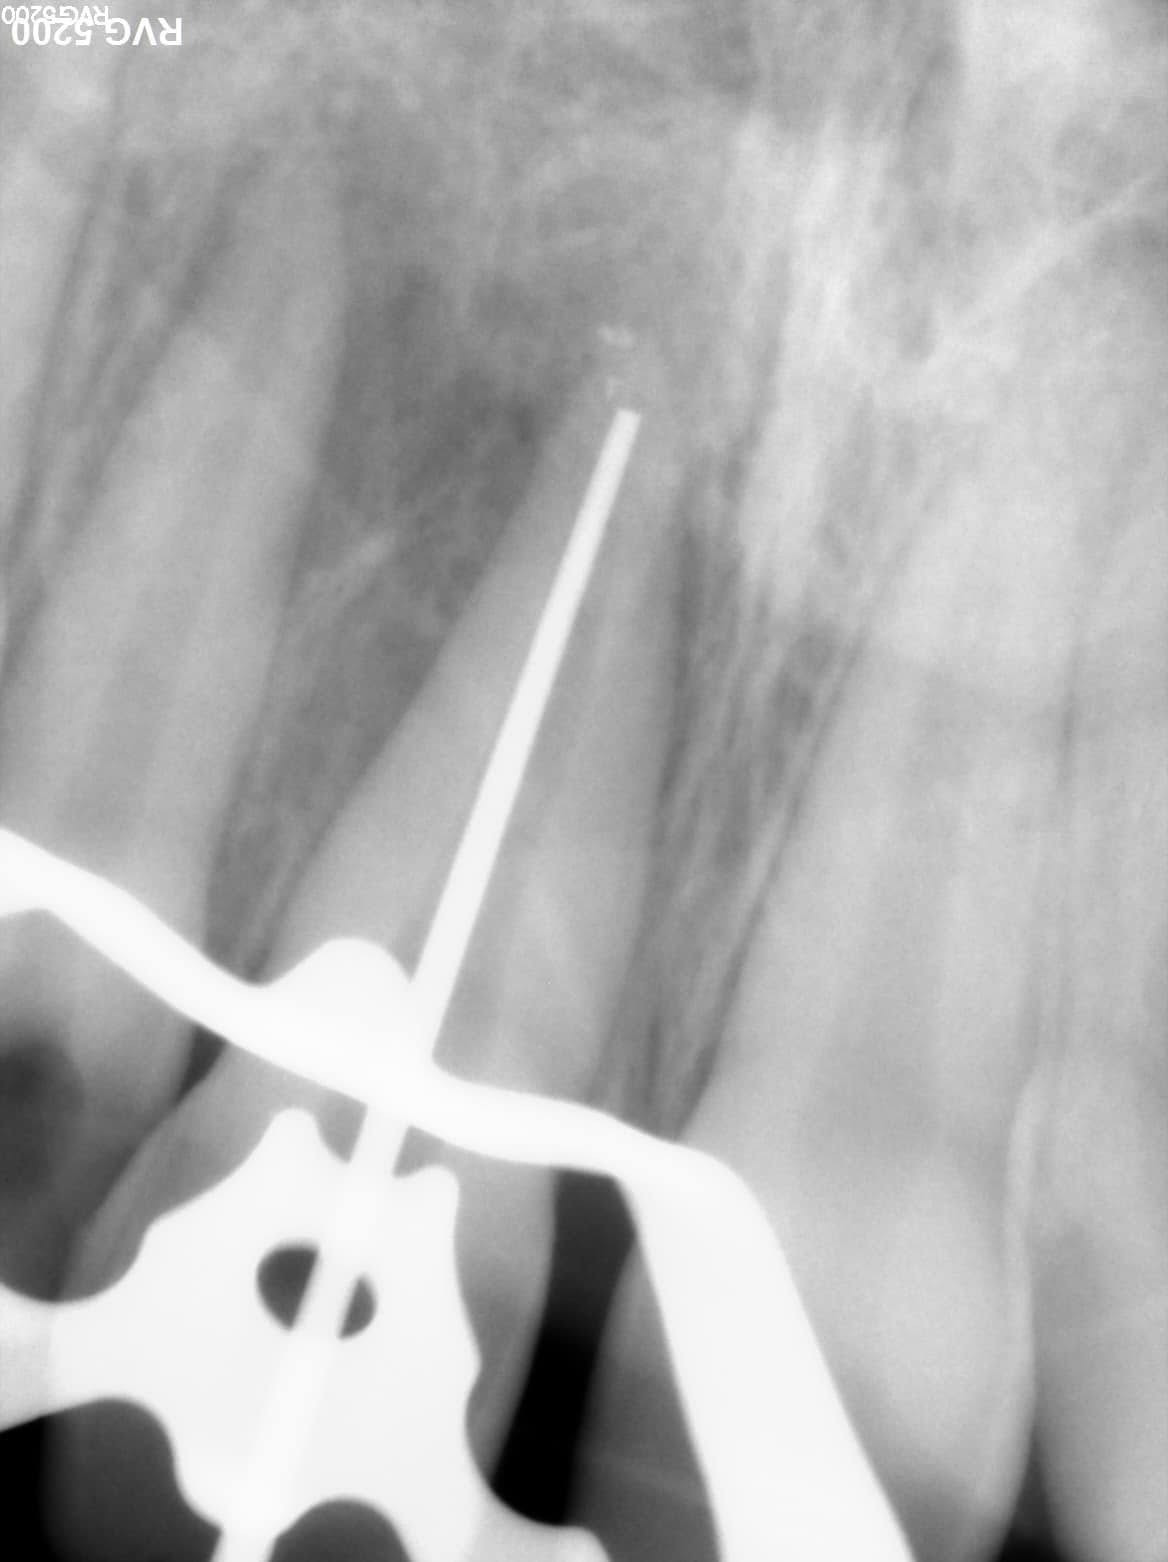

Xray with the plugger reaching the apical area